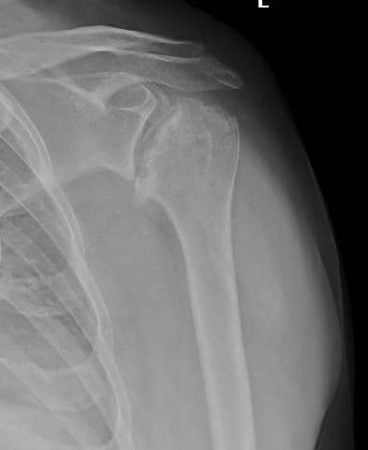

Un tânăr giurgiuvean diagnosticat cu necroză a capului humeral,în luna noiembrie 2023, a primit șansa la o viață normală, după implantarea unei proteze de umăr în cadrul serviciului de ortopedie și traumatologie.

Este de menționat faptul că acest tip de intervenție chirurgicală se face doar într-un număr limitat de unități medicale din Romania.

La doar două luni de la intervenție, tânărul este recuperat în proporție de 80%.